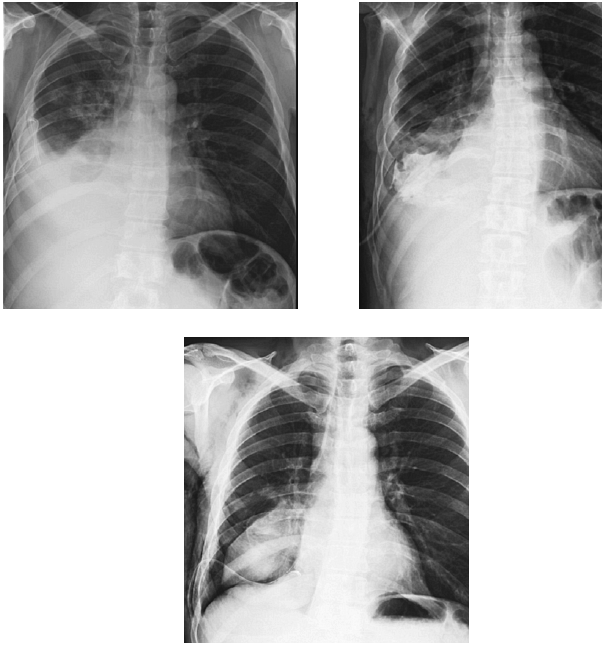

При цитологическом исследовании пунктата обнаружены клетки аденокарциномы. По данным выполненной МСКТ, имелись признаки периферического образования правого легкого с метастатическим поражением лимфатических узлов корня легкого, диффузный пневмосклероз, малый гидроторакс справа (рис. 3, 4).

Рис. 3. Рентгенологическая картина пациента М. при первичном обращении (выпот в плевральной полости) и после дренирования плевральной полости (наличие опухоли)

Рис. 4. КТ-картина образования правого легкого с выпотом в правой плевральной полости у пациента М.